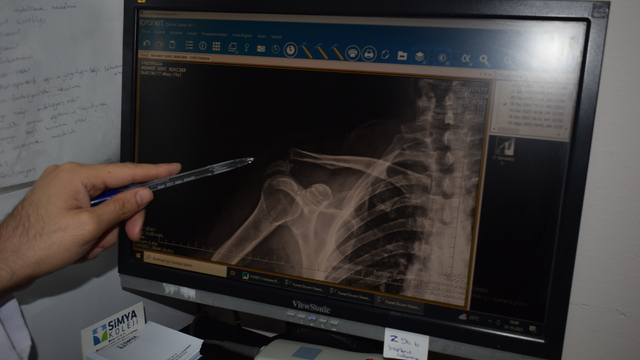

Kentteki bir kortta düştükten sonra omzunda çıkık oluşan Rençber’e, başvurduğu bazı merkezlerde yaş nedeniyle ameliyat önerilmedi. Batman Eğitim ve Araştırma Hastanesi Ortopedi ve Travmatoloji Uzmanı Dr. Mehmet Yavuz Başer’in değerlendirmesi sonrası hasta ameliyata alındı. Rençber’in omzuna kemik yapısına uyumlu, nadir kullanılan özel bir plak takıldı. Ameliyatın ardından fizyoterapi süreci başlatılan hasta, ağrılarının azalmasıyla günlük hareketlerini yapabilir hale geldi ve taburcu edildi.

Ameliyatın başarılı geçtiğini ifade eden Ortopedi ve Travmatoloji Uzmanı Dr. Mehmet Yavuz Başer, “Genelde gençlere ameliyat önerilirken bu hastamıza yaşından dolayı ameliyatlarla ilgili bazı sıkıntılar olduğu anlatılmış. Biz filmlerini gördük. Kendisiyle konuştuk. Muayenesini yaptık. Sosyal olarak aktif birisi olduğu için ameliyat kararını daha uygun gördük. Ameliyatı çok şükür güzel geçti, başarılı geçti. Nadir kullanılan bir plaktan kullandık. O da hastamıza tam olarak uydu. Hastamızın ameliyatı başarıyla geçti. Bundan sonraki süreci de hızlı bir şekilde eski haline kavuşturacağız inşallah 3 hafta içinde. Fizik tedavi sürecini başlattık. Şu anda birçok hareketi yapabiliyor. Biraz ağrıları geçince inşallah eski haline kavuşacak. Hastamızı bugün inşallah pansumanını ve tedavisini yaptıktan sonra taburcu edeceğiz” dedi.